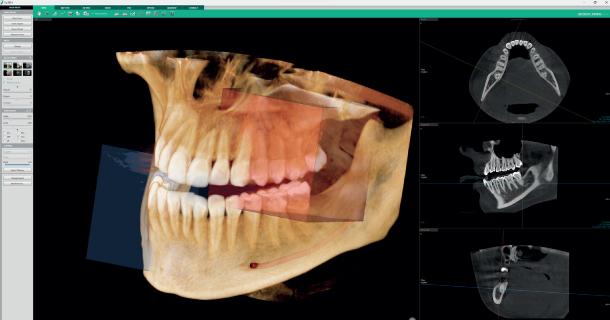

• Назначение: ПАНО + КЛКТ + СКАНЕР МОДЕЛЕЙ

• Размер поля обзора при кт (см): 4×4 , 8×5, 8×8, 12×9 см, Опция: 12x14

Smart Focus 1 сканирование = 5 изображений

С Green X 12 за одно сканирование вы получите 5 изображений высокого разрешения нескольких областей. Одно КТ-изображение 12х9, одну автопанораму и три КТ-изображения 4х4 повышенной четкости в выбранной области интереса.

Green X12 предлагает широкий выбор полей обзора. Multi FOV позволяет пользователям выбирать оптимальный размер области сканирования, сводя к минимуму облучение тех участков, которые выходят за пределы области интереса. Варианты полей обзора включает в себя следующие размеры: 12x9, 8x8, 8x5 и 4x4. Эти варианты охватывают всю область дуги, синус и левый/правый ВНЧС и подходят для большинства случаев челюстно-лицевой хирургии и операций с несколькими имплантатами.

Полный зубной ряд 12x9

Оптимальный размер для покрытия всего зубного ряда